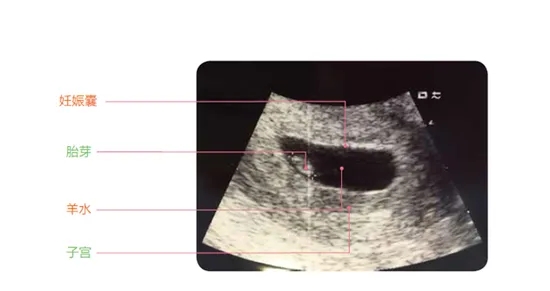

2.、B超檢查

當(dāng)然,除了驗(yàn)血,也有的醫(yī)生可能會(huì)讓做B超檢查,但也可能因?yàn)樘鞌?shù)太少,醫(yī)生會(huì)給開陰超檢查,相比來說,陰超要比腹部B超看的更清楚些。

這個(gè)階段,醫(yī)生會(huì)重點(diǎn)看 孕囊(一般是在孕30-40天孕囊出現(xiàn)),醫(yī)生會(huì)根據(jù)“孕囊的大小、位置、性狀”等,來判斷胚胎是否在正常發(fā)育。

① 孕囊大小

這里說的“孕囊大小”,指的是孕囊的直徑,在懷孕6周時(shí)孕囊的直徑約為2cm。

② 孕囊形狀和位置

不少人,在懷孕早期會(huì)根據(jù)孕囊的性狀來判斷懷的男孩還是女孩,其實(shí)這是沒科學(xué)道理的,不過在這個(gè)階段,的確可以通過B超看孕囊的性狀是“橢圓形還是圓形”,而醫(yī)生會(huì)根據(jù)孕囊的性狀、位置等判斷胎兒的發(fā)育情況。